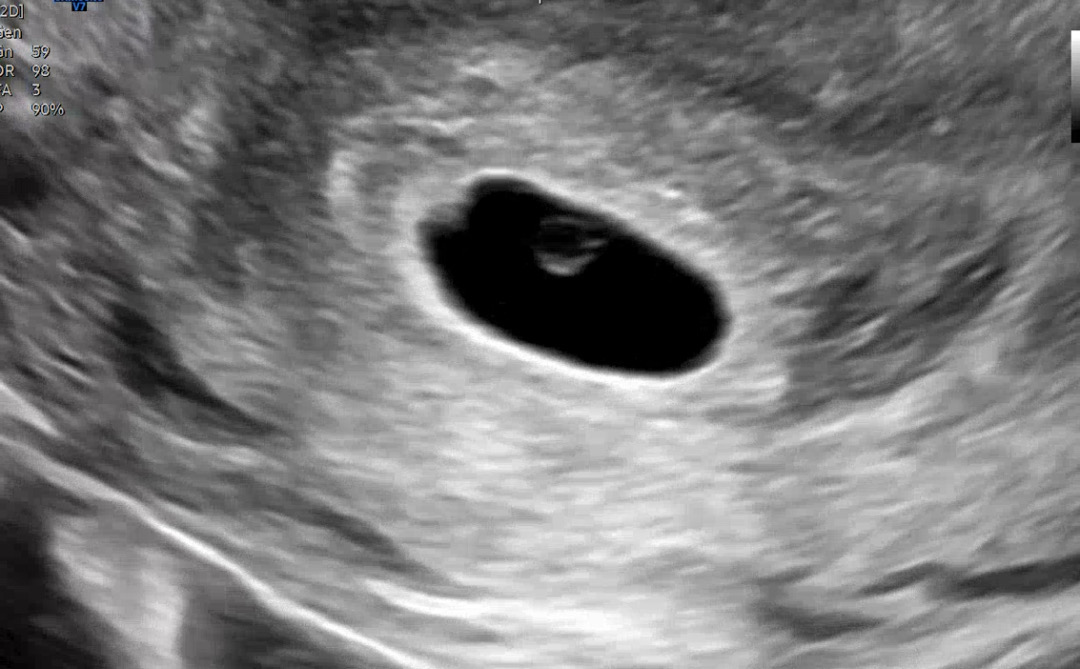

5.16일 배란 오늘 아기집 보고왔어요!

난황까지 보고왔습니다 ㅎㅎ 2주뒤 심장소리 들으러가요 ㅎㅎㅎㅎ